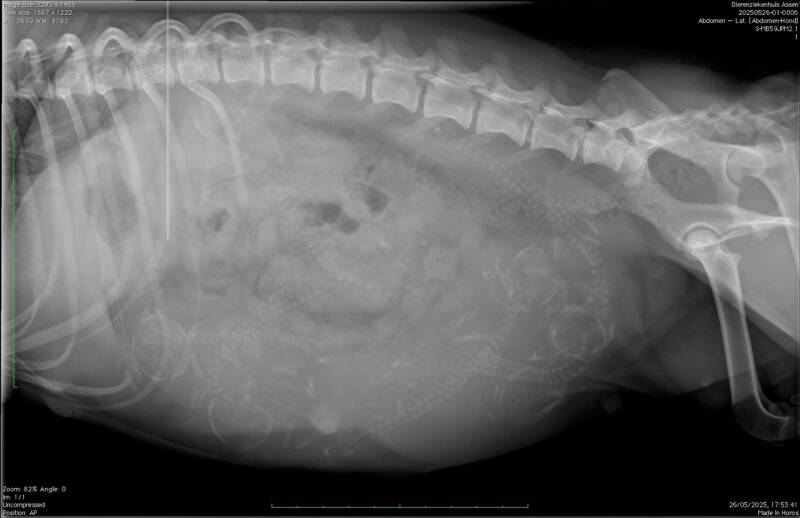

Vandaag stond de Röntgen foto op de planning.

En onze Britt verwacht 6 lieve kleine puppy's. ❤️Wij hebben er zin in. Er is nog plek voor de wachtlijst ❤️